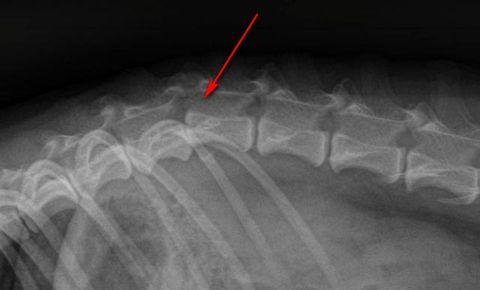

Остеохондроз позвоночника — это дегенеративное заболевание, затрагивающее межпозвонковые диски. Оно приводит к ослаблению фиброзного кольца и его разрушению под воздействием пульпозной ткани. Развитие этой патологии происходит постепенно и имеет четко выраженные этапы.

На начальном этапе, из-за нарушений кровообращения и обмена веществ, пульпозное ядро начинает высыхать. Это приводит к смещению межпозвонковых дисков вниз и образованию микроскопических трещин в фиброзном кольце. Смещение дисков ослабляет и провисает мышечные ткани и связки, что снижает фиксацию позвонков и увеличивает вероятность их смещения даже при незначительных нагрузках. Этот процесс вызывает нестабильность в позвонково-двигательной системе. На этой стадии массаж оказывается наиболее эффективным, так как он способствует укреплению мышечной фиксации позвонков.